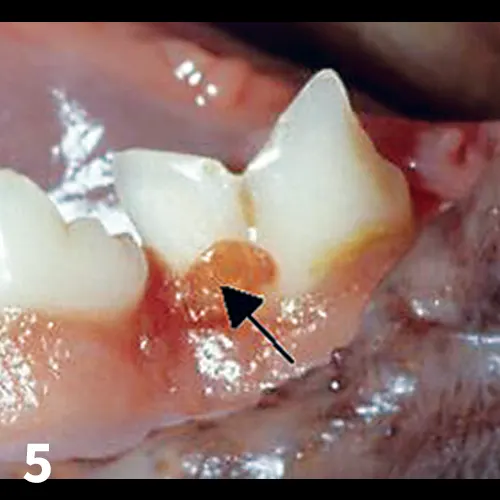

Tooth resorption is a form of external resorption. Resorption is the loss of hard tissues caused by cells called odontoclasts; external resorptions starts in the root’s cementum layer and can extend into the dentin. Previously called cervical neck lesions, feline caries, and feline odontoclastic resorptive lesions (FORLs), tooth resorption affects 25% to 75% of the cat population over age 2.11  The odontoclasts, which are derived from hematopoietic stem cells, migrate from the blood cells of the periodontal ligament space toward the external root surface and start destroying the dental hard tissue.11 (See Figures 5-7.)

FIGURE 5

Tooth resorption: Note the granulation tissue growing into the enamel defect (arrow)